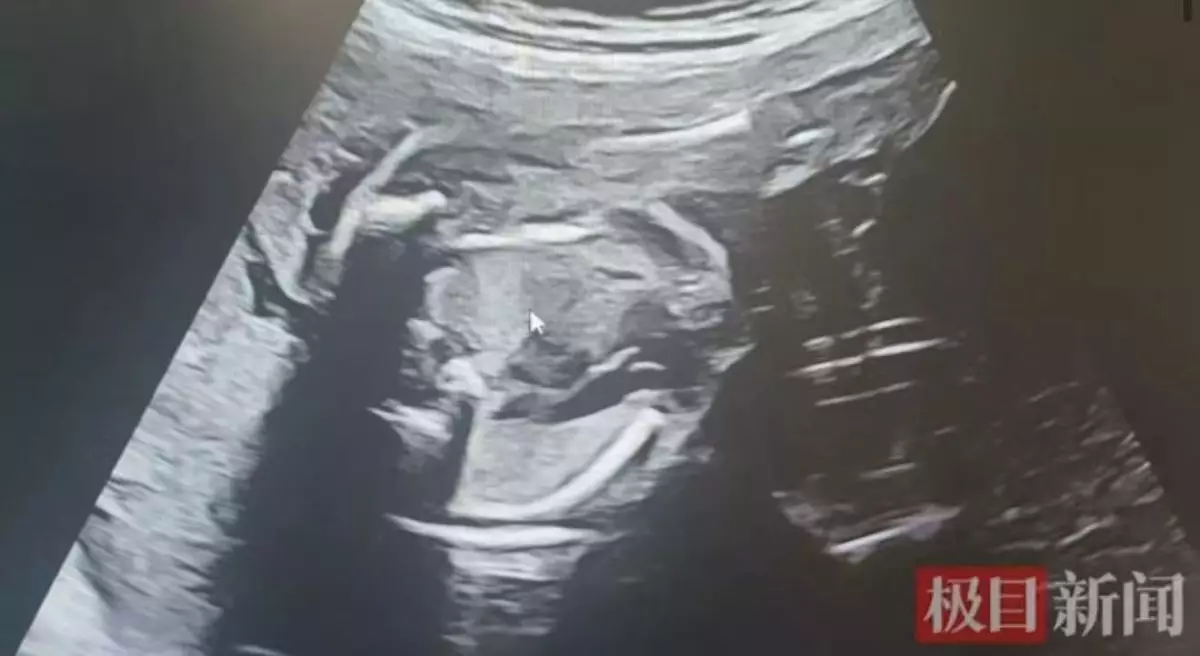

初期檢查尚算平穩,直至孕25周,孟女士突感腹部脹痛難忍,急赴醫院求診。超聲波結果顯示,一名胎兒羊水過多,另一名則幾近枯竭,確診為典型雙胎輸血綜合症。產科主任醫生周潔瓊解釋,共用胎盤上出現異常血管吻合支,導致供血兒血液持續流向受血兒,打破血液平衡,若不及時處理,兩名胎兒均有生命危險。